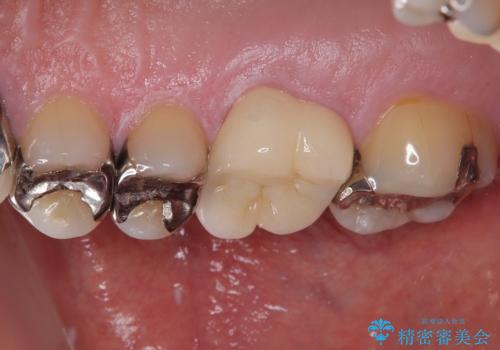

治療途中の奥歯 オールセラミッククラウンでのむし歯治療

根管治療後に痛みの消失を確認し、オールセラミッククラウンにて補綴治療を行うこととしました。

初回の根管治療時に仮歯を装着しましたが、仮歯を介して食事などを行っても痛みは感じなくなっており、その後は速やかに補綴治療を行いました。